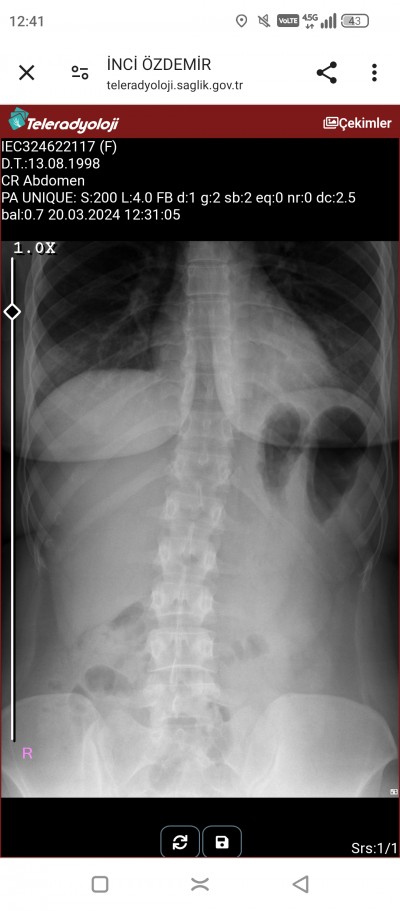

Bugün röntgen çekildim siyah böyle beni korkuttu nedir o acaba bilen varmı